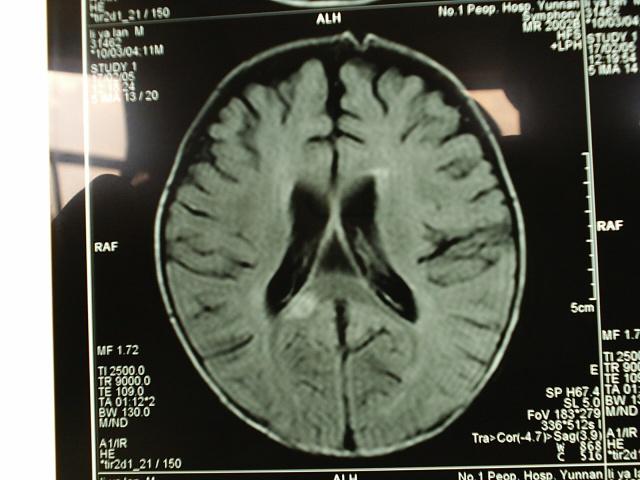

小儿结核性脑膜炎合并脱髓鞘改变MRI

病变部位在右侧大脑半球胼胝体压部强化部分。大家注意看